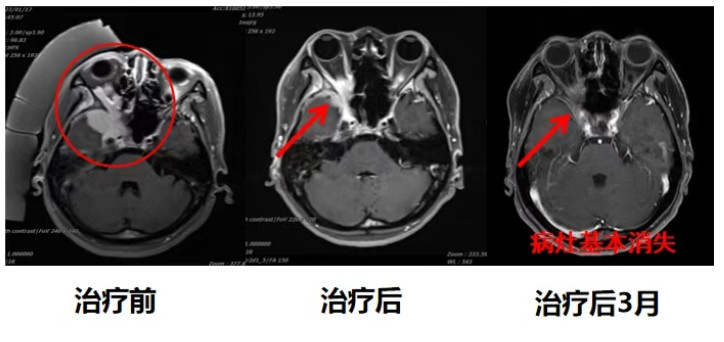

Therapeutic Outcomes

Throughout the treatment course, the tumor located at the inferotemporal region with orbital invasion demonstrated rapid shrinkage. The patient who presented with right eye blindness at admission quickly regained light perception post-treatment. By treatment completion, the tumor had reduced by approximately 70%, achieving Partial Response (PR) efficacy.